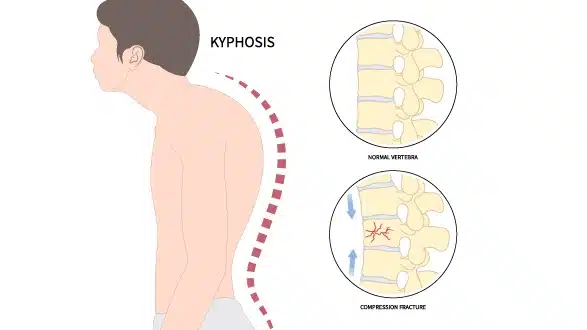

- explain the Kyphosis( hunchback).(કાઇફોસીસને વર્ણવો).

કાયફોસિસ એ સ્પાઇન ની એબનોર્માલીટી છે કે જેમાં સ્પાઇનલ કોડ નું આઉટવર્ડ તરફ કર્વેચર થાય છે.

સ્પાઇનલ કોડૅ એ રાઉંડિંગ ઓર હંચબેક થાય છે.

કાયફોસીસ માં સ્પાઇનલ ની કોન્વેક્સિટી એ આઉટવર્ડ તરફ ઇંક્રીઝ થાય છે.

explain the Etiology of Kyphosis.(કાયફોસિસ ના કારણ વર્ણવો).

- સ્પાઇનની ડીજનરેટિવ ડીઝીઝ ના કારણે.

- ઇન્જરી થવાના કારણે.

- ટ્રોમા થવાના કારણે.

- સ્કોલીઓસીસ.

- એક વરટીબ્રા એ બીજા ઉપર ફોરવર્ડ થવાના કારણે.

- મારફાન સિન્ડ્રોમ.

- ઇન્ફેક્શન થવાના કારણે.

- મસ્ક્યુલર ડિસ્ટ્રોફી.

- ન્યુરો ફાઇબ્રોમાટોસીસ.

- પેગેટ ડિસિસ.

- પોલિયો.

- પુઅર પોસ્ચર.

- એજ.

- ઓસ્ટિયોપોરોસિસ (વીકએનીંગ ઓફ બોન).

- સ્પાઇનલ કોડ માં ઇન્જરી થવાના કારણે.

- કંજીનાઇટલ

- એબનોર્માંલીટી ના કારણે.

- એન્કાઇલોસિસ સ્પોન્ડીલાઇસિસ ના કારણે.

- સ્પાઇના બીફિદા.

- ટ્યુમર એન્ડ એન્ડોક્રાઇન ડિસઓર્ડર

explain the Clinical manifestation/sign and symptoms of kyphosis. (કાઇફોસીસ ના લક્ષણો તથા ચિનહો વર્ણવો)

- પુઅર પોસ્ચર.

- “હંચબેક ” .

- રાઉંડ બૅક અપીરીયન્સ.

- માઇલ્ડ બેક પેઇન થવું.

- શ્વાસ લેવામાં તકલીફ પડવી.

- અપર બેક તથા નેક એરિયામાં બર્નિંગ સેન્સેશન થવું.

- મસલ્સ ફટીગ થવું.

- પલ્મોપરી એન્ડ હાર્ટ ફેઇલ્યોર થવુ.

- સ્પાઇનમાં સ્ટીફનેસ આવવી.

- બોવેલ તથા બ્લેડર કંટ્રોલ એ લોસ થવું.